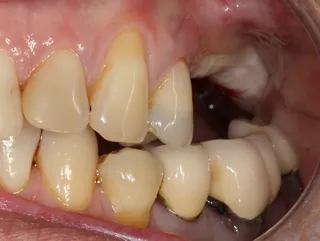

3a-b & 4a-b. Preoperative situation.

Free-end saddle. Periodontal tissue appeared healthy. Plenty of keratinized tissue. Notice the more extensive vestibular bone loss around 25.